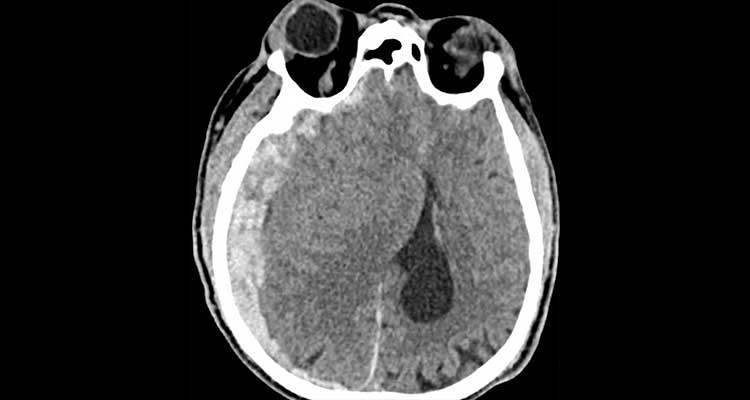

A CT scan of a traumatic brain injury.

CT scan of an older patient with subdural hematoma, a bleed near the brain, which is more common in people over 65 due to normal brain shrinkage that puts pressure on weakened veins. The patient acquired this injury after a ground-level fall.